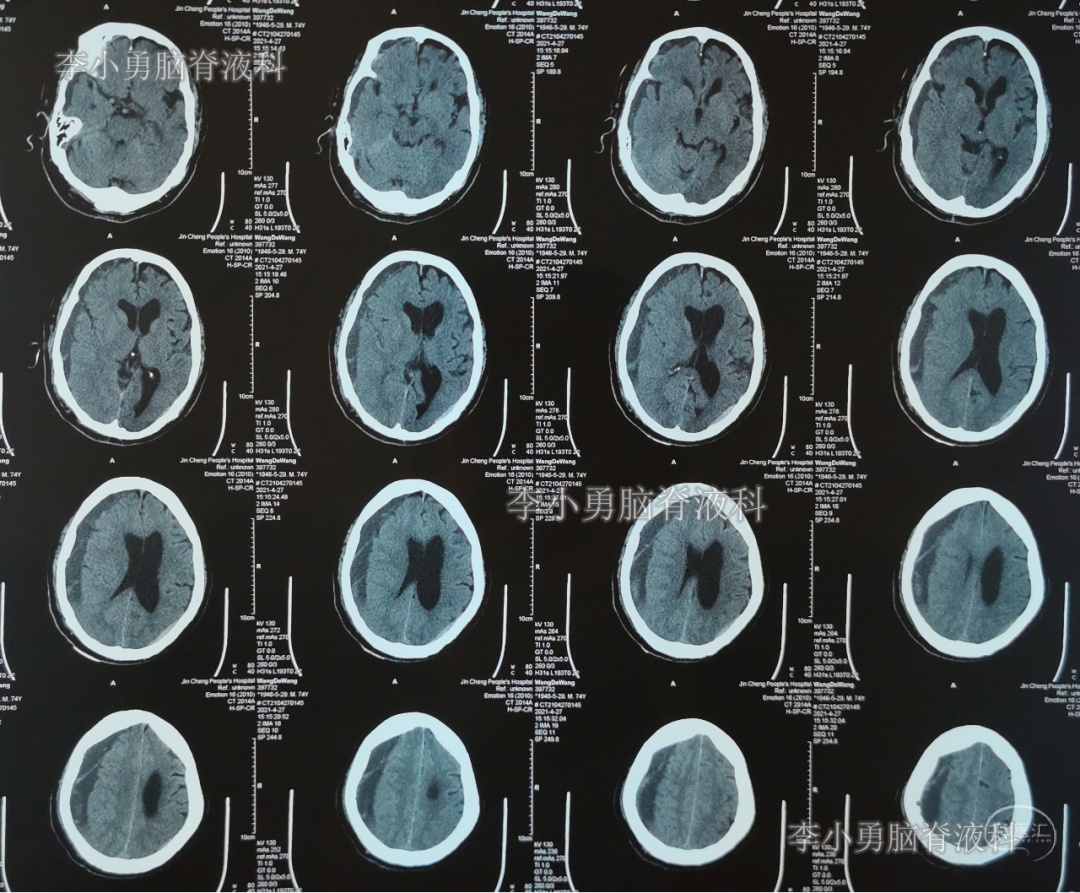

2021年4月30日(腰大池腹腔分流术后33天,即拔除硬膜下血肿引流管11天),因坐立时仍头痛,转至第5家山西省另一所省级三甲医院,查头部CT(图-9)后建议继续平卧位。

图-9:2021年4月30日头部CT

2021年5月5日(腰大池腹腔分流术后38天,即拔除硬膜下血肿引流管16天),查头部核磁和腰椎核磁(图-10、图-11)后认为可能是颅内感染或和堵管。

图-10:2021年5月5日头部核磁

图-11:2021年5月5日腰椎核磁

2021年5月8日(腰大池腹腔分流术后41天,即拔除硬膜下血肿引流管19天)),拔除了腰大池分流管。

术后4天即2021年5月12日,虽能下地行走但腿软,查头部CT(图-12)后“仍有脑积水”。

图-12:2021年5月12日头部CT